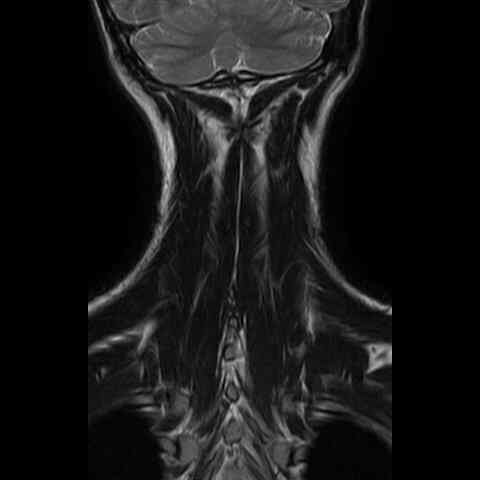

this brain does not look straight...

everything has a twist to it.